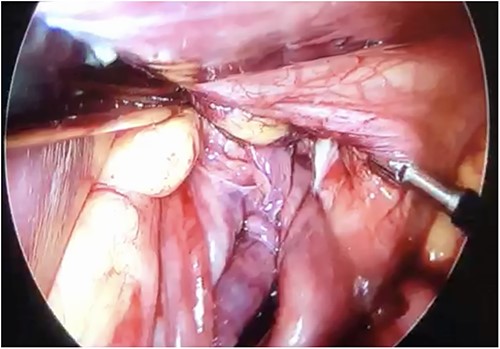

Initial treatment included intravenous crystalloid fluid repositioning, pain management, and antibiotic therapy. After diagnosing perforated gastric volvulus on a computed tomography (CT) scan, a diagnostic laparoscopy was performed. A hiatal hernia was identified with protrusion and twisting of the gastric body (Fig. 2). As the stomach body was reduced back to the abdominal cavity, a 1.5-cm perforation at the level of the greater curvature was detected. It was primarily sutured and covered with an omental patch (Fig. 3). The ischemic hernia sac containing the stomach was filled with food scraps and resected (Fig. 4). Laparotomy conversion was necessary due to hemodynamic instability attributable to the laparoscopic pneumoperitoneum. A 180° anterior fundoplication of the stomach (Dor’s Technic) associated with diaphragmatic raffia was performed. Gastric air leak testing was negative and intraoperative endoscopy showed no other defects on the gastric wall.

Laparoscopic view of the necrotic hernial sac with food scraps inside.